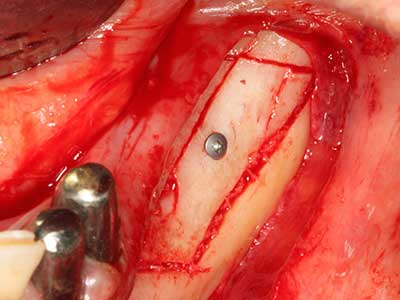

Indicazione: preparazione vicino ai nervi

Come descritto in precedenza, le indicazioni per la piezochirurgia si possono trovare anche nel campo della chirurgia odontoiatrica conservativa. Delle puntine particolari semplificano l'esposizione delle punte delle radici e facilitano la protezione dei nervi e delle membrane mucose del seno, in particolare nella regione dentale superiore e posteriore e in quella premolare inferiore. Le puntine angolate diamantate si utilizzano per preparare con precisione la cavità della resezione che ospiterà il materiale di riempimento della radice retrograda per l'otturazione apicale sigillata. Grazie alla tecnologia a ultrasuoni le puntine possono essere estremamente sottili, quindi la visibilità e le dimensioni di accesso della cavità sono migliori. Di conseguenza, l'applicazione della chirurgia a ultrasuoni per questa indicazione è una delle procedure standard per la resezione apicale (Del Fabbro, Tsesis et al. 2010, Scarano, Artese et al. 2012).

Indicazione: resezione apicale

Quando le procedure chirurgiche vengono eseguite sull'osso nelle immediate vicinanze di strutture sensibili, come vasi sanguigni o nervi, gli strumenti rotanti pongono un rischio significativo di lesione iatrogena. I dispositivi piezoelettrici possono essere utili per la preparazione delle coperture ossee e la rimozione del tessuto duro in prossimità dei nervi, in particolare per la loro esposizione dopo una lesione iatrogena, ma anche durante la lateralizzazione dei nervi per le procedure di resezione e ricostruzione o il posizionamento di impianti (figg. 17-20). Il contatto leggero tra puntina piezoelettrica e nervo non causa generalmente danni, ma se si procede senza prestare attenzione con movimenti a sega o raccordi con residui di substrati ossei possono verificarsi danni al nervo temporanei o anche permanenti. Il rischio di danno, tuttavia, è considerato sostanzialmente inferiore al rischio presente utilizzando seghe o frese (Pereira, Gealh et al. 2014).